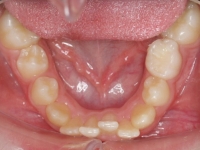

El paciente A.J. de 11 años, acude a nuestra consulta con apiñamiento maxilar importante. El canino lateral (12) está en mordida cruzada. Presenta una Clase II molar y canina, y la línea media está desviada. Se realizó un tratamiento con brackets autoligables metálicos de smartclip 022. La duración del tratamiento fue de 22 meses.

El paciente actualmente ha terminado el tratamiento con brackets y lleva una contención fija de 2-2 en maxilar y 3-3 en mandibular; para complementar también lleva una férula ESSIX durante la noche.

INICIO FINAL